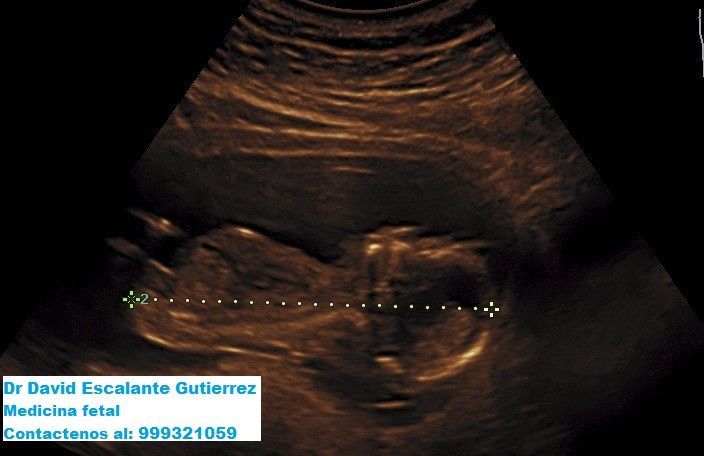

Servicios Ecográficos de Alta Calidad

Realizamos las ecografías de viabilidad del embarazo, genética, morfológica, de bienestar fetal, ecocardiografías fetales, así como procedimientos invasivos como biopsia de vellosidades coriales y amniocentesis.